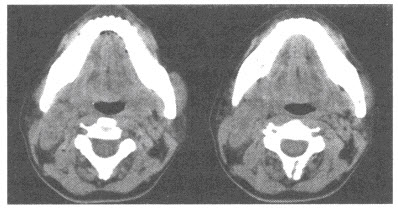

17、单项选择题

男,37岁,自觉颌下肿物7年。CT检查如图,应诊断为()

A.颌下皮样囊肿

B.颌下神经鞘瘤

C.颌下淋巴结结核

D.甲状舌管囊肿

E.以上均不是